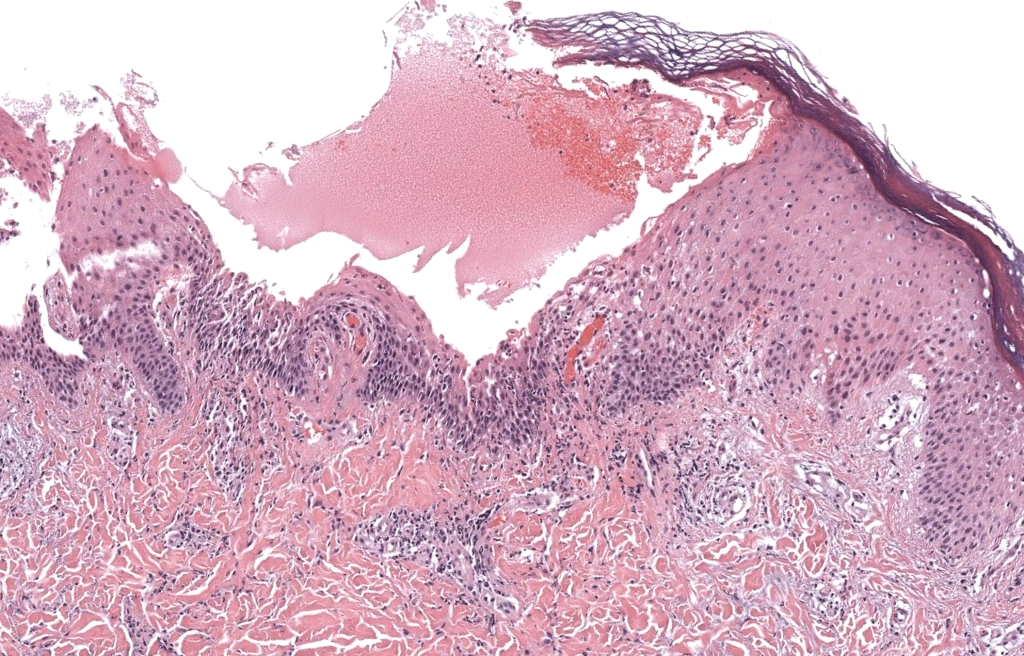

- Histología necesaria

- Biopsia de pústula reciente con gran pústula subcórnea neutrofílica.

- Ausencia de hiperplasia psoriasiforme típica y de vasculitis franca.

- Tinciones especiales negativas para hongos y bacterias significativas.